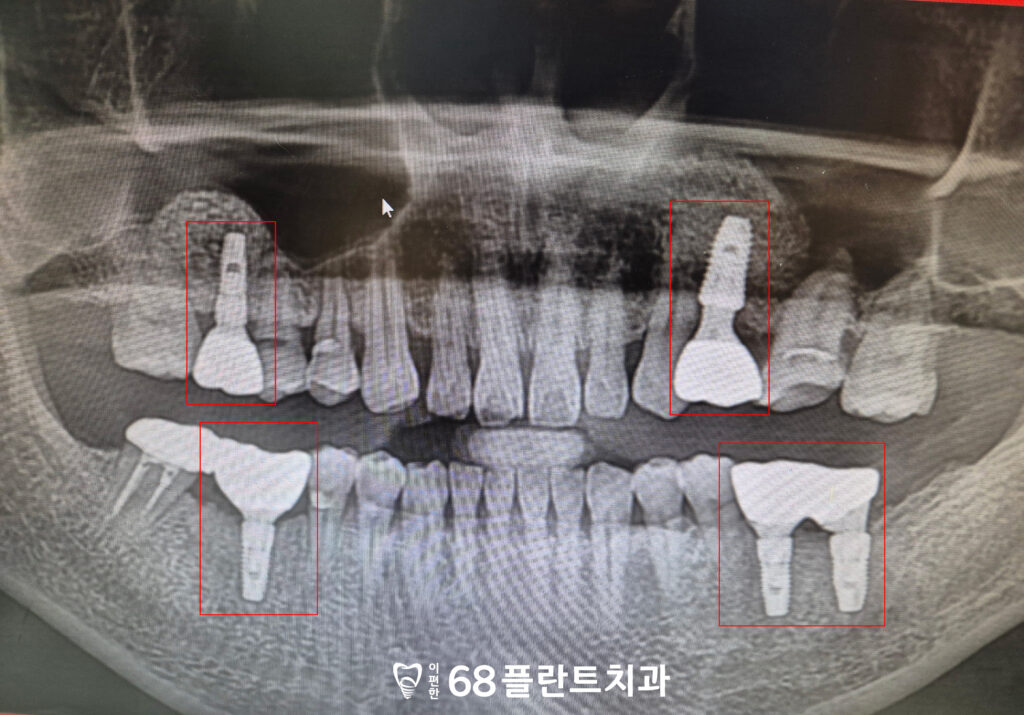

이렇게 환자분의 치아 상실 부위에는

임플란트를 식립하는 동시에,

부족한 뼈 높이를 보강하기 위해

상악동거상술을 함께 진행하였습니다.

이를 통해 임플란트가

안정적으로 자리 잡을 수 있는

튼튼한 기반을 마련할 수 있었으며,

장기적으로 저작 기능과 심미성을 회복하는 데

도움이 되도록 치료가 이루어졌습니다.

◆ 전 > 후 ◆

치료가 모두 마무리된 후

환자분께서는 그동안 여러 개의 치아가 상실되어

제대로 씹지 못하고 식사할 때마다

불편함을 느끼셨지만,

임플란트 치료와 상악동거상술을 통해

이제는 다양한 음식을 골고루 드실 수 있게 되었다며

큰 만족감을 표현하셨습니다.